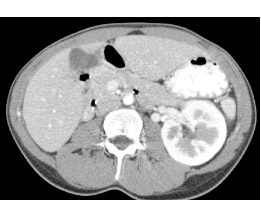

Note the difference in appearance of the renal cortex and medulla on Images C and D. This is because the scan was done very soon after injection of contrast into an arm vein. The cortex lights up before the medulla, just as the aorta is higher attenuation than the IVC.